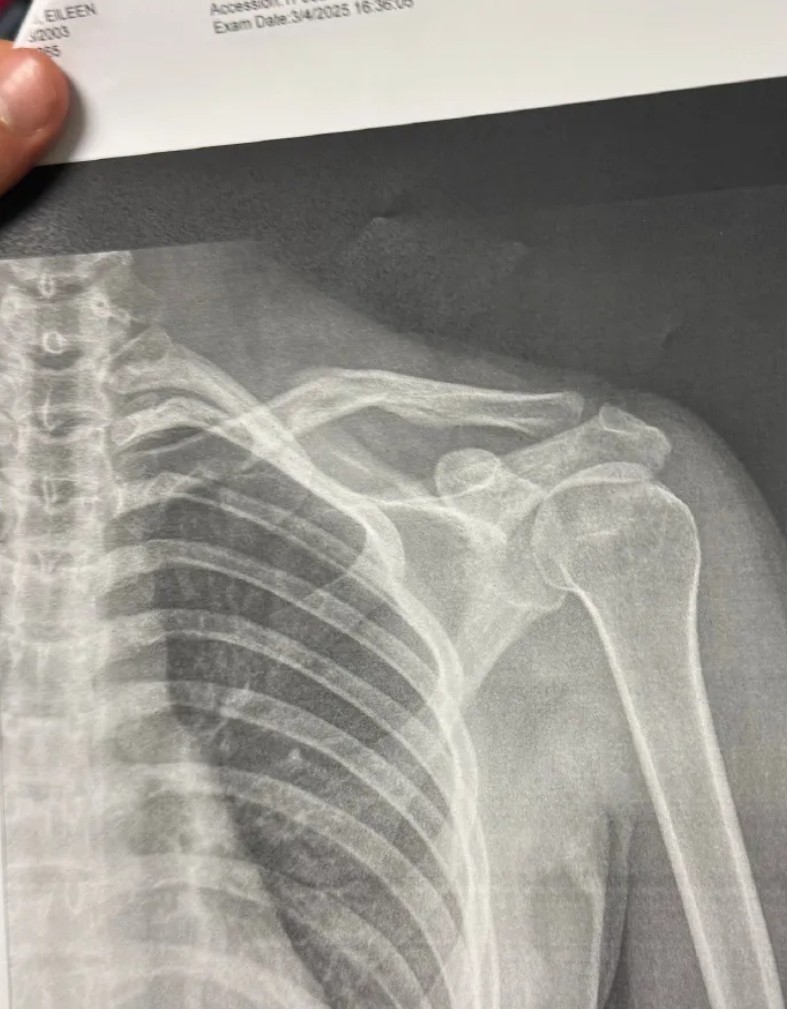

谷爱凌受伤骨折图

急性期过后,她转入一个更需耐心的阶段——功能性康复。这远非“养伤”,而是对身体进行系统性再教育。以肩部骨折为例:

第1-4周:

在严格的制动中,治疗师已开始通过神经肌肉电刺激,维持肩周肌肉的活性,对抗萎缩。

第5-8周:

在康复师手势的引导下,进行如钟摆般轻柔的关节活动度训练,重新探索疼痛的边界。

第8周后:

开始使用弹力带进行多角度的抗阻训练,精细重建前举、外旋等滑雪专属动作的肌肉记忆。